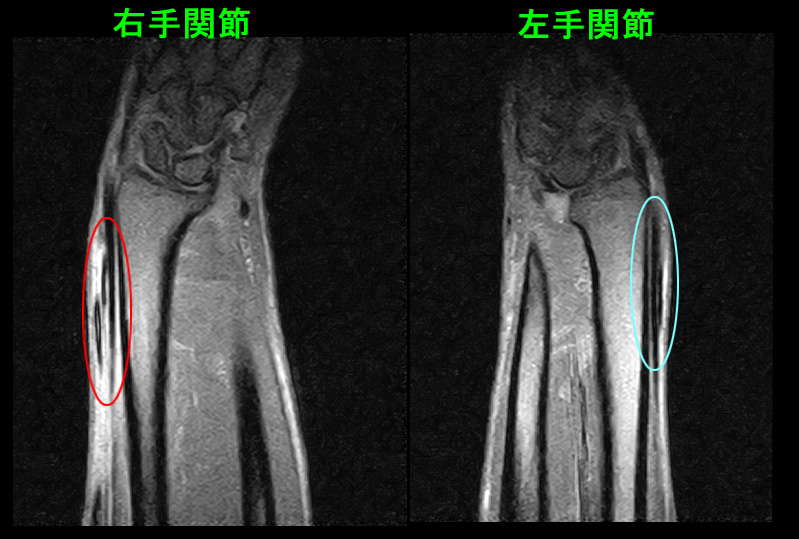

57才男MR2.jpg

このMRI所見は腱の炎症部分を水平に切った断面となりますが、赤丸領域で2本の腱の上に1本の腱(母指外転筋腱)が交差しており、その周囲が白く炎症の状態にあります。